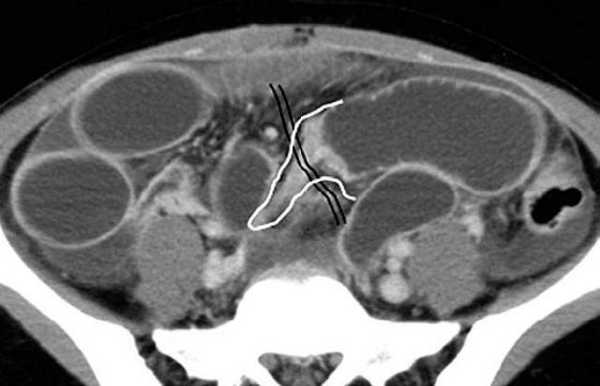

(в, г) Петли тонкой кишки (прямые стрелки) лежат в левой половине брюшной полости, а ободочная кишка (изогнутые стрелки) — в правой половине. Заворот средней кишки у мальчика 11 лет.

Врожденная мальротация кишечника обусловлена нарушением нормальной ротации первичной кишки в направлении против часовой стрелки. Среди широкого разнообразия вариантов мальротации в клинической практике наиболее часто встречают полное отсутствие ротации (нонротация). При этом состоянии тощая кишка служит прямым продолжением двенадцатиперстной, при этом отсутствуют 3-й и 4-й сегменты двенадцатиперстной кишки и двенадцатиперстно-тощекишечный переход. Петли тонкой кишки лежат в левой половине брюшной полости, а ободочная кишка — в правой половине. При завороте средней кишки ножка брыжейки сужена, а двенадцатиперстно-тощекишечный переход (местонахождение связки Трейтца) чаще расположен низко, по правую сторону от средней линии. Такие условия приводят к перекручиванию неправильно фиксированной тонкой кишки, а верхние брыжеечные артерия и вена располагаются в короткой и суженной ножке брыжейки.

Также выявляют эктопию основной части петель тонкой кишки и патологическое расположение связки Трейтца.